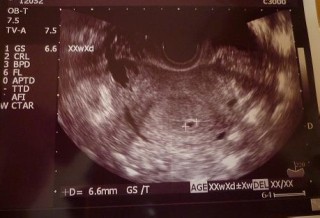

初めて病院受診したときの写真です。4w6dだったのでまだ見えないかなーと思ったら、6.6mmの胎嚢が見えました。